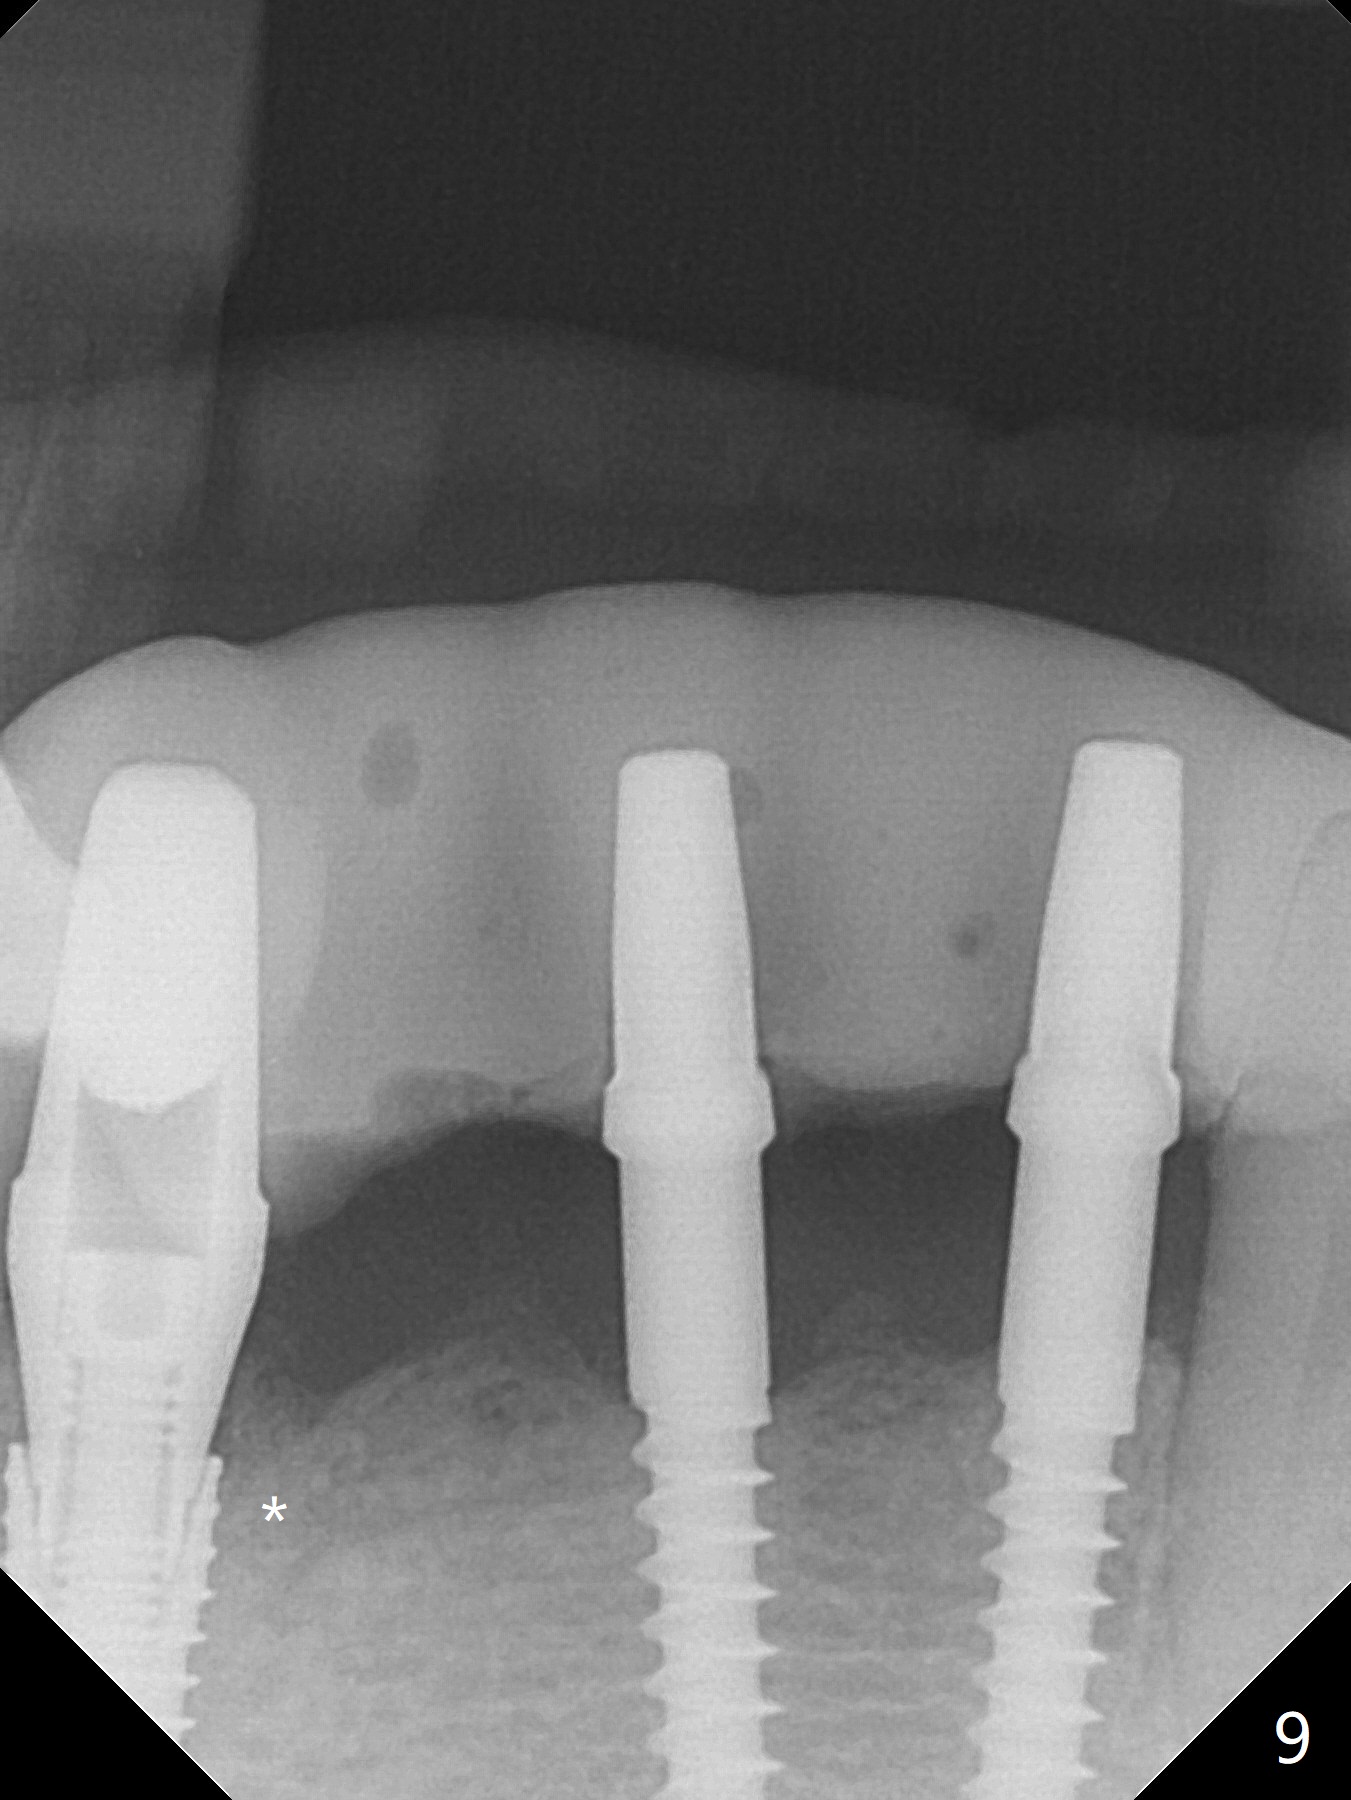

The mesial defect at #27 appears to have been repaired 8 months postop (Fig.8,9 *); there is no bone loss at 1-piece implant sites. The gingival recession seems to remain the same before and after removal of the provisional FPD (Fig.10,11). The bulging abutment at the cervix is less prominent when a straight abutment is used and prepared (Fig.12, 4.5x5.5(5) mm). There is no bone loss at #23, 25 and 27 sites 2.5 years post cementation (Fig.12-15), although the trajectory of the implants could be improved by using surgical guide (Fig.16-18).